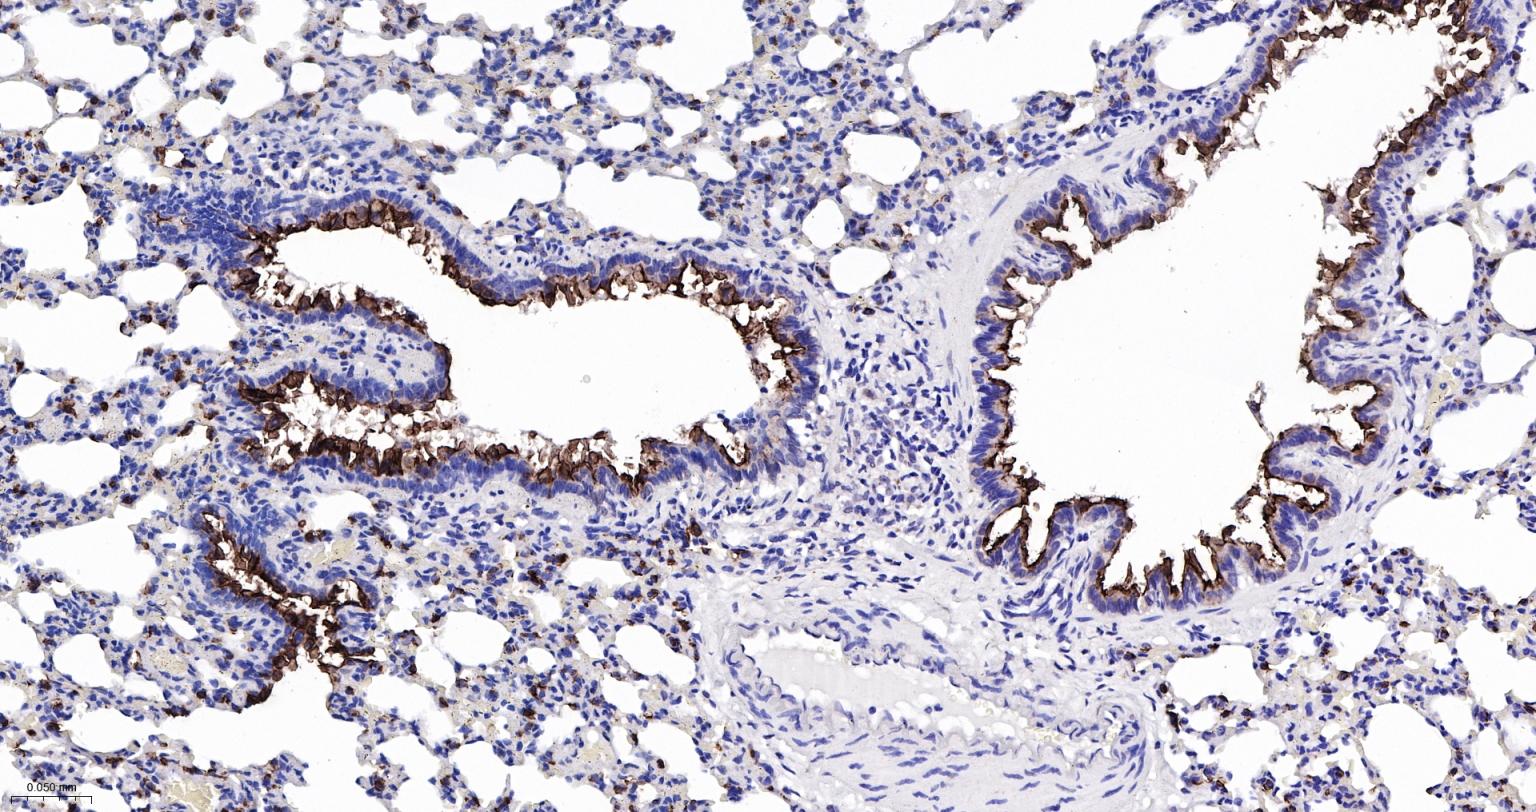

Paraformaldehyde-fixed, paraffin embedded Mouse Lung; Antigen retrieval by boiling in sodium citrate buffer (pH6.0) for 15 min; Antibody incubation with MUC1 Monoclonal Antibody, Unconjugated(bsm-52576R) at 1:200 overnight at 4°C, followed by conjugation to the bs-0295G-HRP and DAB (C-0010) staining.